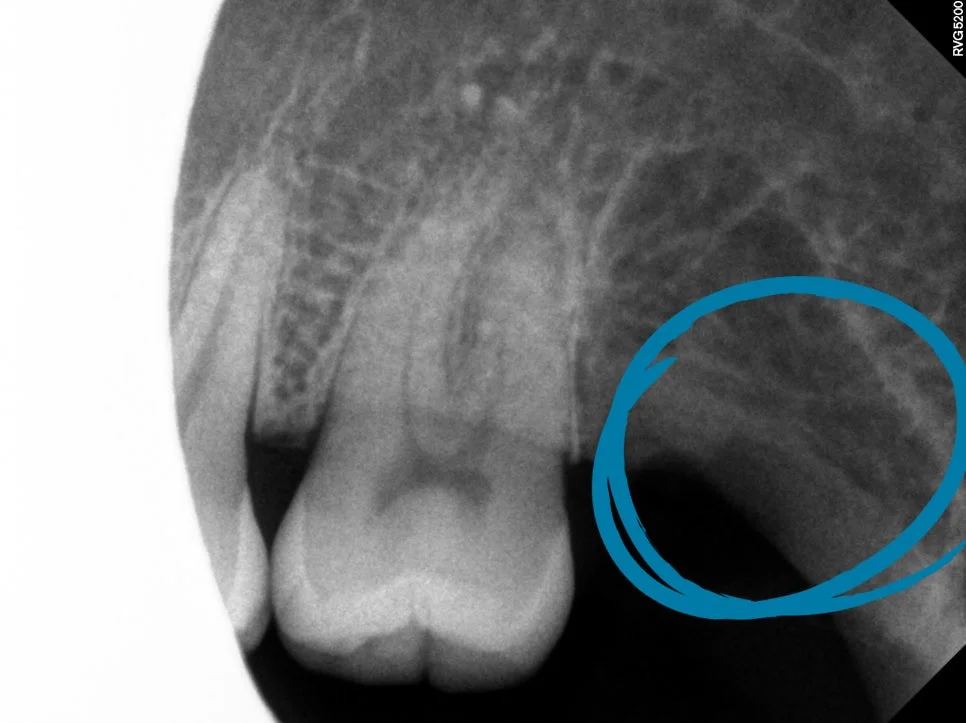

CBCT 진단 — 신경관 위치 사전 확인

CT를 보면 사랑니가 신경관과 꽤나 가까이 맞닿아 있는 상태가 확인되었습니다.

이런 경우에는 CT 검사가 선택이 아니라 필요한 과정인데요. 정확한 영상을 통해 발치 동선을 사전에 계획할 수 있어 신경 손상과 같은 위험 요소를 대폭 줄일 수 있습니다.

사랑니가 신경관에 가까울수록 하치조신경 손상 위험이 있기 때문에 사전 CBCT(3D CT) 검사가 필수입니다. 정확한 영상을 통해 발치 동선을 사전에 계획할 수 있어 신경 손상 위험을 대폭 줄일 수 있습니다. 서울쏙쏙치과에서는 CT를 통해 신경관 위치를 확인한 후 안전한 경로를 설계하여 발치합니다.